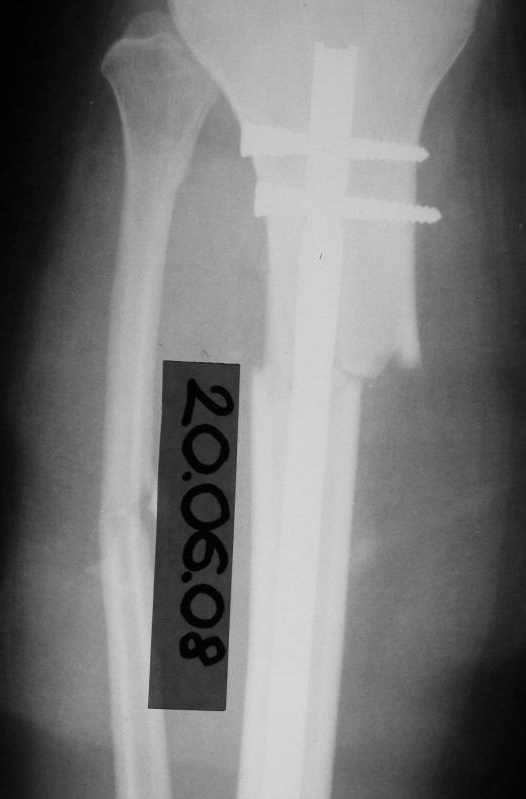

Имя     : 20.06.08.JPG

Тип     : image/jpeg

Размер  : 14888 байтов

Url     : http://weborto.net:8080/pipermail/ortho/attachments/20090417/b6bc8f23/attachment-0006.jpeg

голени в/3 со смещением. В ПДО ПХО раны,вытяжение за пяточную кость. После заживления раны

20.06.08 выполнен остеосинтез блокирующем стержнем. в течение первого месяца после травмы

сохранялась субфебрильная температура на фоне приема антибиотиков. Затем температура